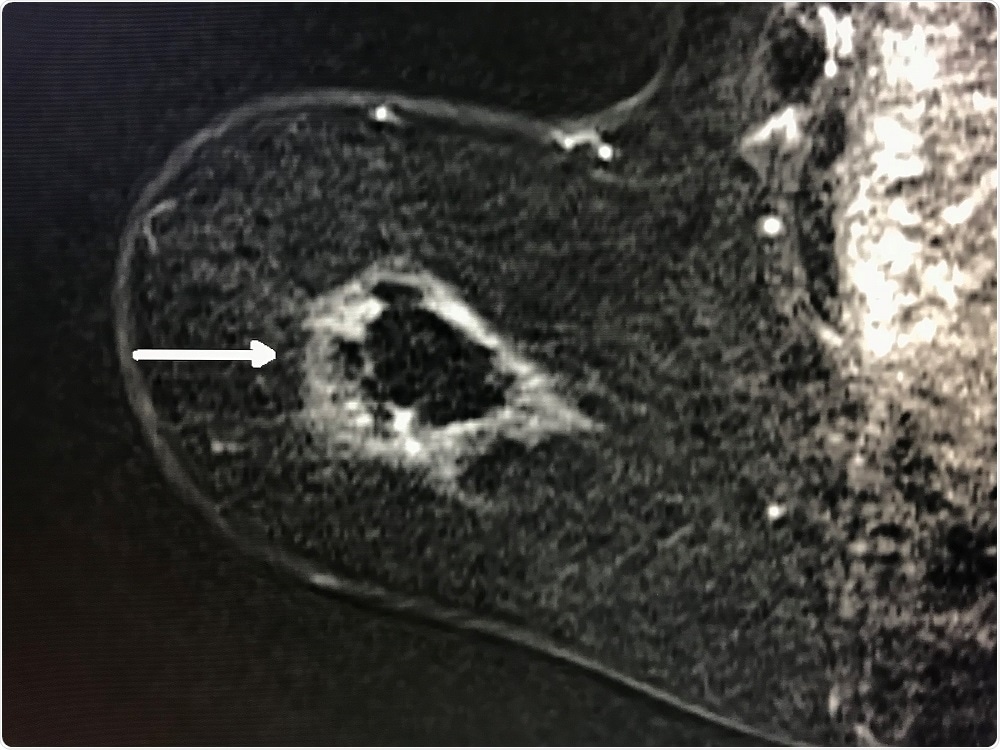

Breast cancer cells targeted in cyroablation - Radiological Society of North AmericaMRI post ablation shows white outline of ablation zone referred to as "cryohalo" with normal dark breast tissue centrally and no evidence of residual cancer (arrow). (Radiological Society of North America)